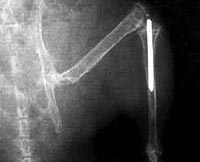

Un joven austríaco lleva prótesis en los brazos dirigidas por su cerebro